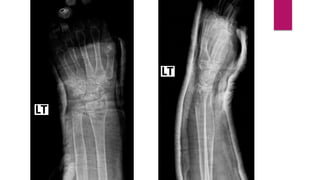

• Film Left wrist AP, Lateral

• Left distal end radius fracture (Fernandez type I)

Investigation • Film Leftwrist AP, Lateral

Diagnosis • Left distalend radius fracture (Fernandez type I)